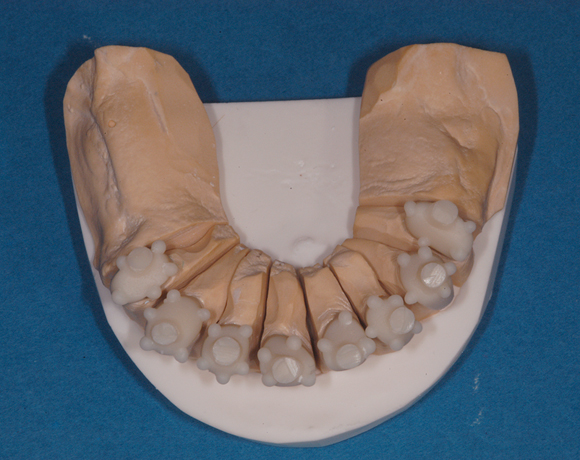

Üblicherweise werden Teleskopkronen aus Metalllegierungen hergestellt. Der Nachteil dieser Prothesenkonstruktion für den Patienten ist, wenn er seine Prothese aus dem Mund nimmt sieht man nur noch gold- oder silberfarbene Zahnstümpfe. Mit den Innenteleskopen aus e.max Press sieht man zahnfarbene Stümpfe, die unserem ästhetisches Verständnis nicht gleich ins Auge stechen.

Im vorliegenden Patientenfall musste eine komplette Neukonstruktion der Oberkieferversorgung vorgenommen werden, da auf Grund parodontaler Probleme die Seitenzahnbrücken 15 – 17 und 25 – 27 nicht mehr zu halten waren. Die verbliebenen acht Frontzähne bzw. Prämolaren waren auch parodontal vorgeschädigt und es war ungewiss wie lange sie einzelne noch halten lassen. Um nicht bei jedem Verlust eines der Restzähne eine Neukonstruktion zu brauchen, hat man sich für eine Teleskopprothese entschieden. Für den Patienten war es allerdings nicht vorstellbar goldfarbene Primärteile im Mund zu haben, so wurde der Versuch unternommen diese aus e.max Press und Galvano Sekundärteilen herzustellen.